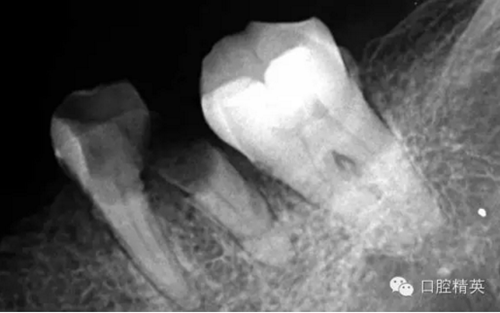

這個(gè)也是我目前接到最有難度的器械分離病例,從片子上看近中器械分離兩節(jié),曾在外院做過(guò)干尸,有七年。當(dāng)看到這個(gè)病例時(shí)我沒(méi)有多大的把握,因?yàn)槲沂巧硖幓鶎?,無(wú)顯微,無(wú)放大。我只有抱著試一試的態(tài)度,但是她是我們?cè)簝?nèi)員工,壓力很大。

現(xiàn)在開(kāi)始看第二張片子我疏通的遠(yuǎn)舌根,有點(diǎn)問(wèn)題哦!~

根尖孔偏移,或者是片子角度問(wèn)題,導(dǎo)致我們很難判斷,感覺(jué)像是測(cè)穿。但是我們有根測(cè)儀(前提它是好的),因?yàn)楦鶞y(cè)儀是我們目前對(duì)根管測(cè)量最具有說(shuō)服力,也是最為客觀事實(shí)的。根測(cè)儀沒(méi)有顯示一探入根尖下三分之一顯示“over”的情況(我用的是登士博根測(cè)儀)根管內(nèi)無(wú)滲出,可以測(cè)出根管的長(zhǎng)度。那就證明工作長(zhǎng)度的存在,和可信。在看看正題的近中根的器械,我想問(wèn)問(wèn)大家覺(jué)得是什么器械??